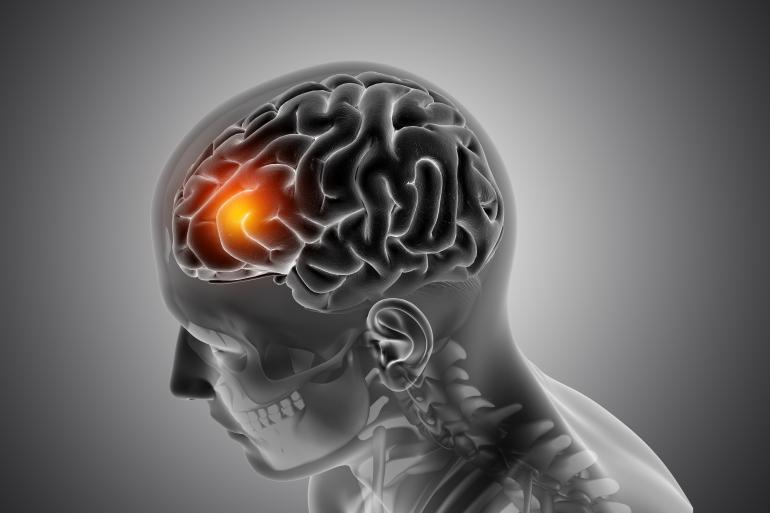

Setembro é o mês de conscientização sobre o aneurisma cerebral. A iniciativa visa educar a população acerca dessa doença silenciosa que pode levar à morte se não for diagnosticada e tratada a tempo.

De acordo com o neurocirurgião Adriano Moraes, o aneurisma cerebral ocorre devido a uma dilatação anômala em um vaso sanguíneo do cérebro. Entre as causas para o surgimento da doença, o médico destaca a herança genética, a pressão alta e o hábito de fumar.

Ainda segundo o especialista, o aneurisma cerebral acomete entre 2% e 5% da população, sendo mais grave quando há o rompimento que leva ao sangramento ao redor do cérebro, podendo deixar sequelas graves ou levar à morte em até 30% dos casos.